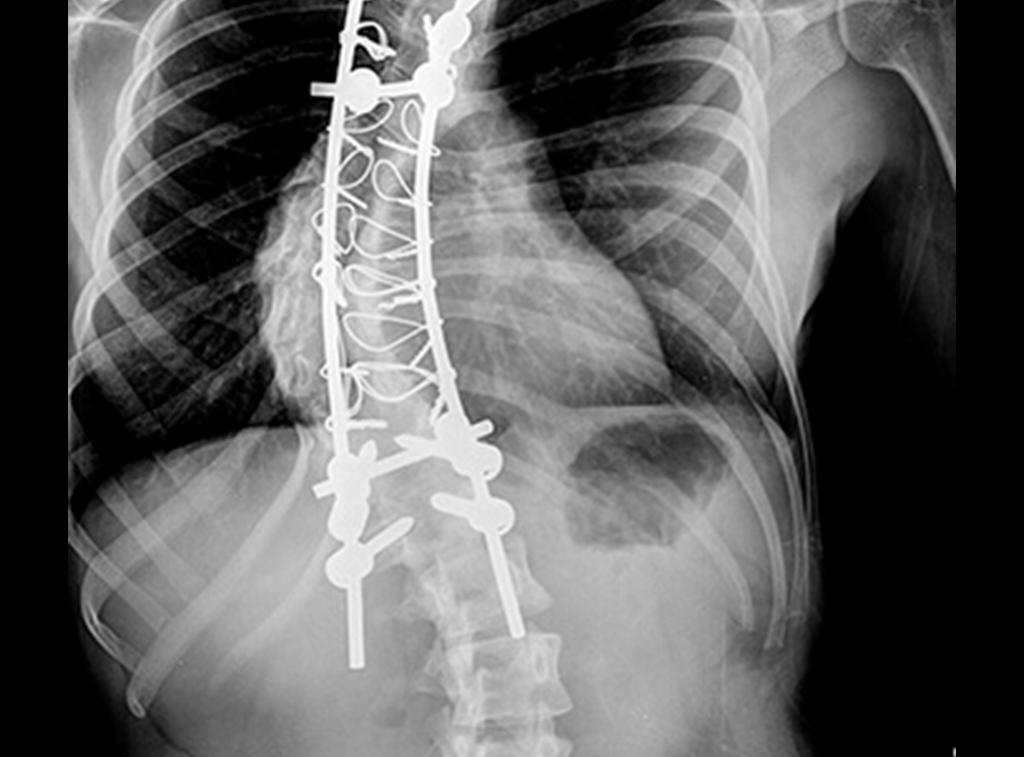

Cirugía

Cirugía Ortopédica y Traumatología

Prótesis ortopédicas

Implantes ortopédicos de columna

Cirugía de columna

Escoliosis y Xifosis

Esto sucede cuando se genera una deformidad en la columna vertebral.